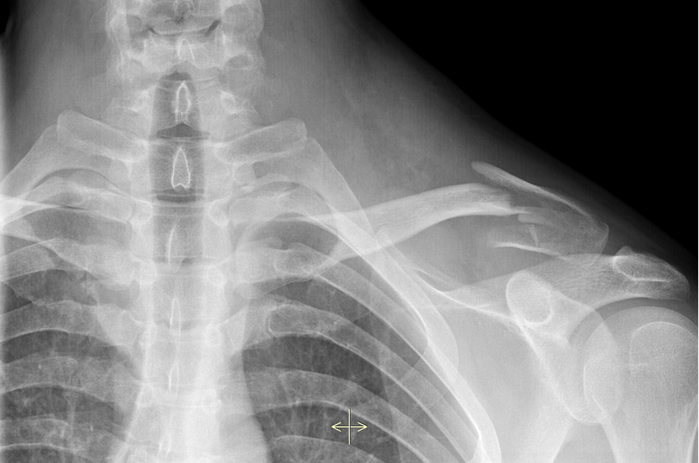

Algumas das doenças mais comuns na área de ortopedia relacionadas ao ombro e cotovelo incluem:

Para lesões mais graves, pode ser necessário infiltração e/ou tratamento cirúrgico. Existem várias opções de cirurgia para lesões e a indicação da cirurgia vai depender do tipo e da gravidade dela. Confira algumas delas.